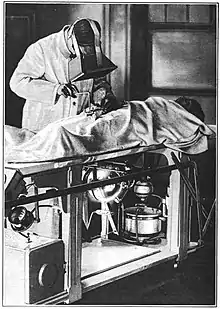

Early radiologists would adapt their eyes to view the dim fluoroscopic images by sitting in darkened rooms, or by wearing red adaptation goggles. After the development of X-ray image intensifiers, the images were bright enough to see without goggles under normal ambient light.[4] Image Intensifiers are still being used to this day (2023) with many new models still using II (Image Intensifier) as its method of acquiring the image which is still popular due to lower cost compared to Flat Panel Detectors and there have been many debates on whether II or Flat Detector is more sensitive to X-Ray, which results in lower X-Ray Dosage used. (Depending upon what type of technology / panel is being used influences this answer greatly)

Fluoroscopy's origins and radiography's origins can both be traced back to 8 November 1895, when Wilhelm Röntgen, or in English script Roentgen, noticed a barium platinocyanide screen fluorescing as a result of being exposed to what he would later call X-rays (algebraic x variable signifying "unknown"). Within months of this discovery, the first crude fluoroscopes were created. These experimental fluoroscopes were simply thin cardboard screens that had been coated on the inside with a layer of fluorescent metal salt, attached to a funnel-shaped cardboard eyeshade which excluded room light with a viewing eyepiece which the user held up to his eye. The fluoroscopic image obtained in this way was quite faint. Even when finally improved and commercially introduced for diagnostic imaging, the limited light produced from the fluorescent screens of the earliest commercial scopes necessitated that a radiologist sit for a period in the darkened room where the imaging procedure was to be performed, to first accustom his eyes to increase their sensitivity to perceive the faint image. The placement of the radiologist behind the screen also resulted in significant dosing of the radiologist.

Red adaptation goggles were developed by Wilhelm Trendelenburg in 1916 to address the problem of dark adaptation of the eyes, previously studied by Antoine Beclere. The resulting red light from the goggles' filtration correctly sensitized the physician's eyes prior to the procedure, while still allowing him to receive enough light to function normally.